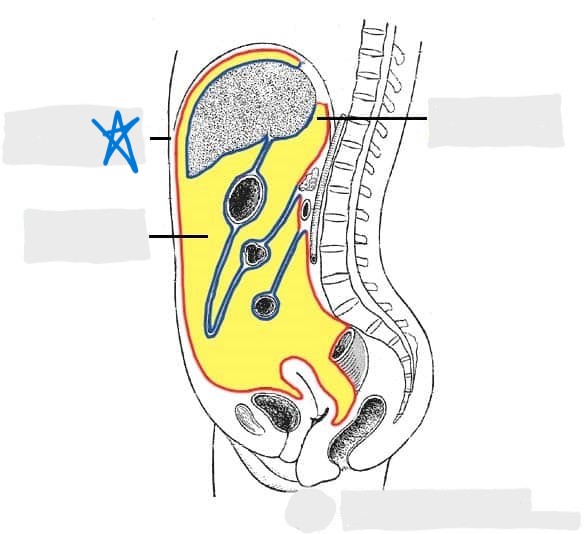

visceral peritoneum

parietal peritoneum

abdominal cavity

pelvic cavity